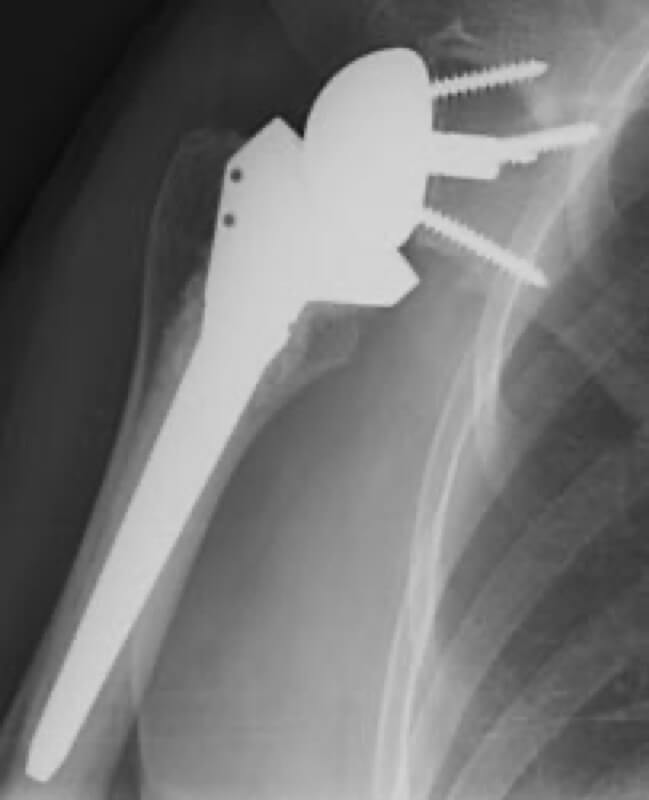

DePuy, Delta